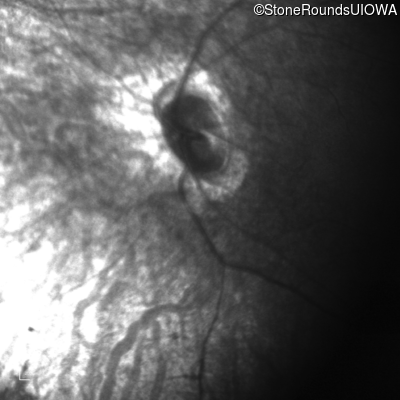

Infrared Fundus Photograph - Right - Light Perception

Exemplar